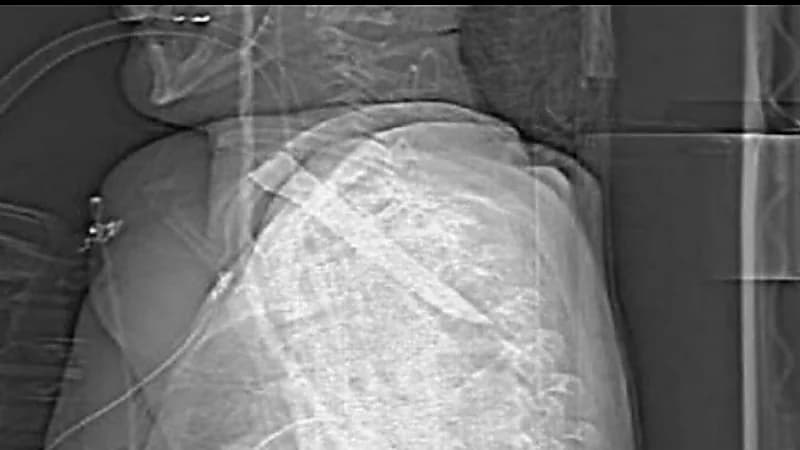

نجا رجل بريطاني من الموت بأعجوبة بعدما تعرض للطعن مما أدى لغرس نصل سكين طولها خمس بوصات ونصف في عنقه، ومن المتوقع أن تكون الطعنة قد تسببت له في إعاقة طويلة الأمد

وأفادت التقارير بأن توماس برازيل البابغ من العمر 28 عامًا اندفع نحو الضحية بسكين مطبخ وطعنه في قاعدة رقبته، حيث أن مقبض السكين انقطع وظل النصل مستقرًا في جسده.

وقال المدعي العام، للمحكمة، أن الضحية خضع لعملية جراحية طارئة لإزالة نصل السكين بعد الحادث في شيلدون، مقاطعة دورهام.